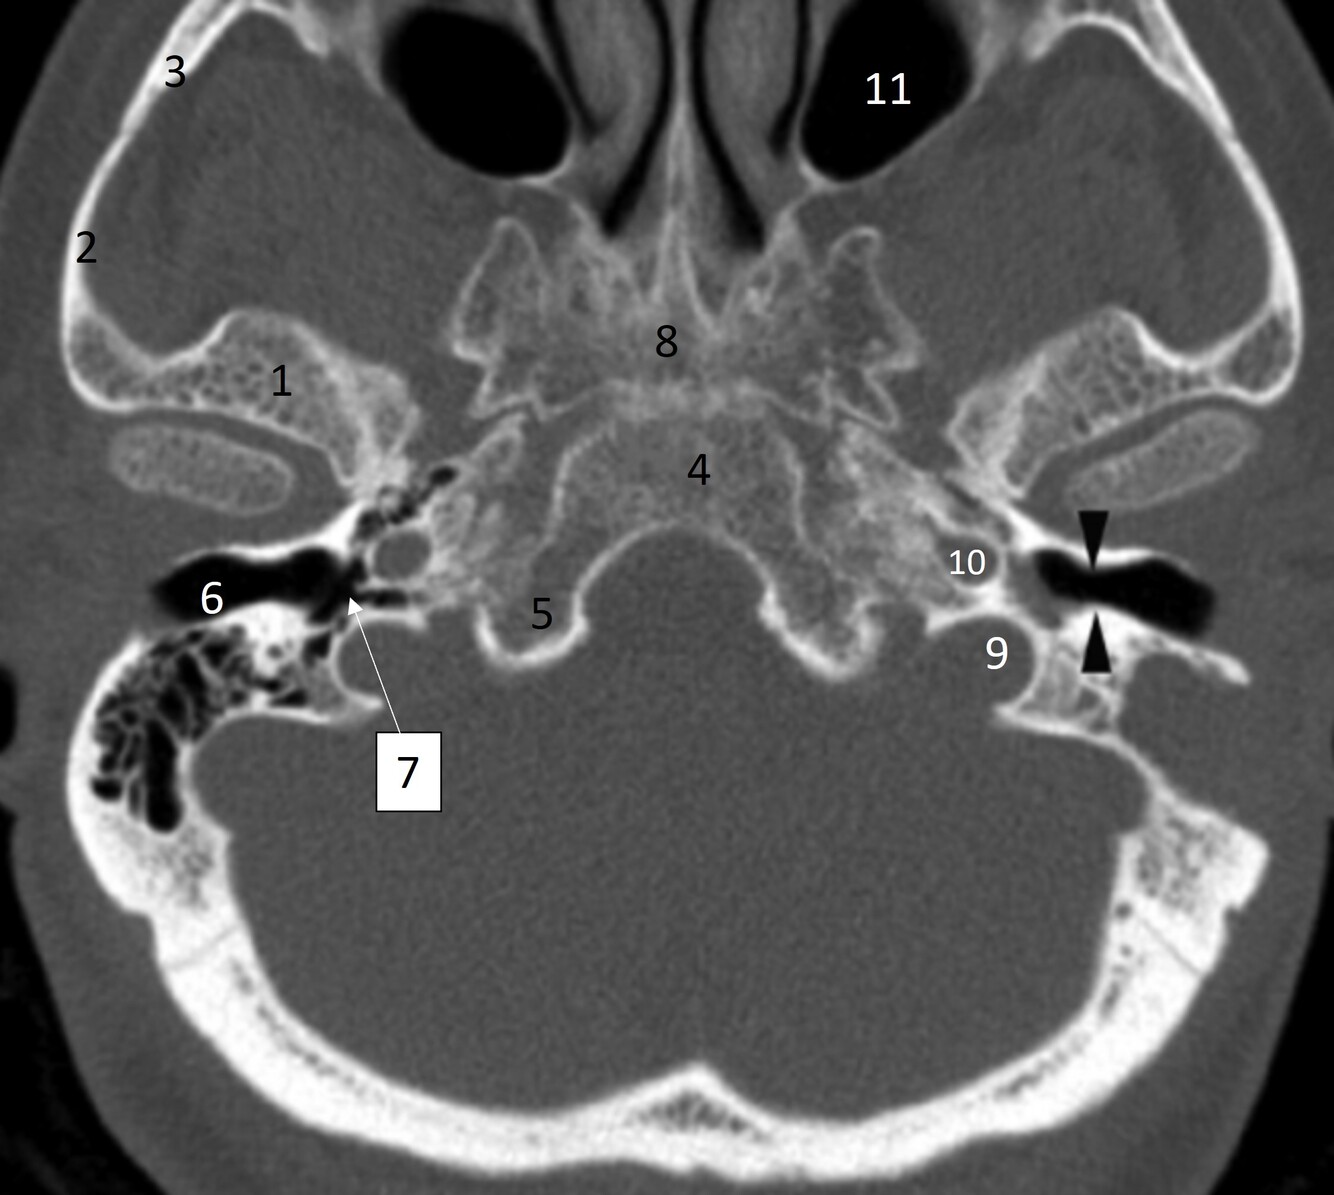

20

Label 36,37,46,62

36=Rt. Inferior nasal concha

37=Lt. Inferior nasal meatus

46=Lt. carotid canal

62= Lt. EAM

22

Q

What narrowing are the black arrowheads pointing at?

A

Isthmus of Rt EAC

23

Label 1-6

1=Rt temporal bone

2=Rt Zygomatic process (temporal bone)

3=Rt Temporal process (zygoma)

4=Clivus

5=Occipital bone

6=Rt EAC

24

Label 7-11

7-Rt middle ear/tympanic cavity

8=Sphenoid

9=Lt jugular foramen

10.=Lt carotid canal

11=Lt maxillary sinus